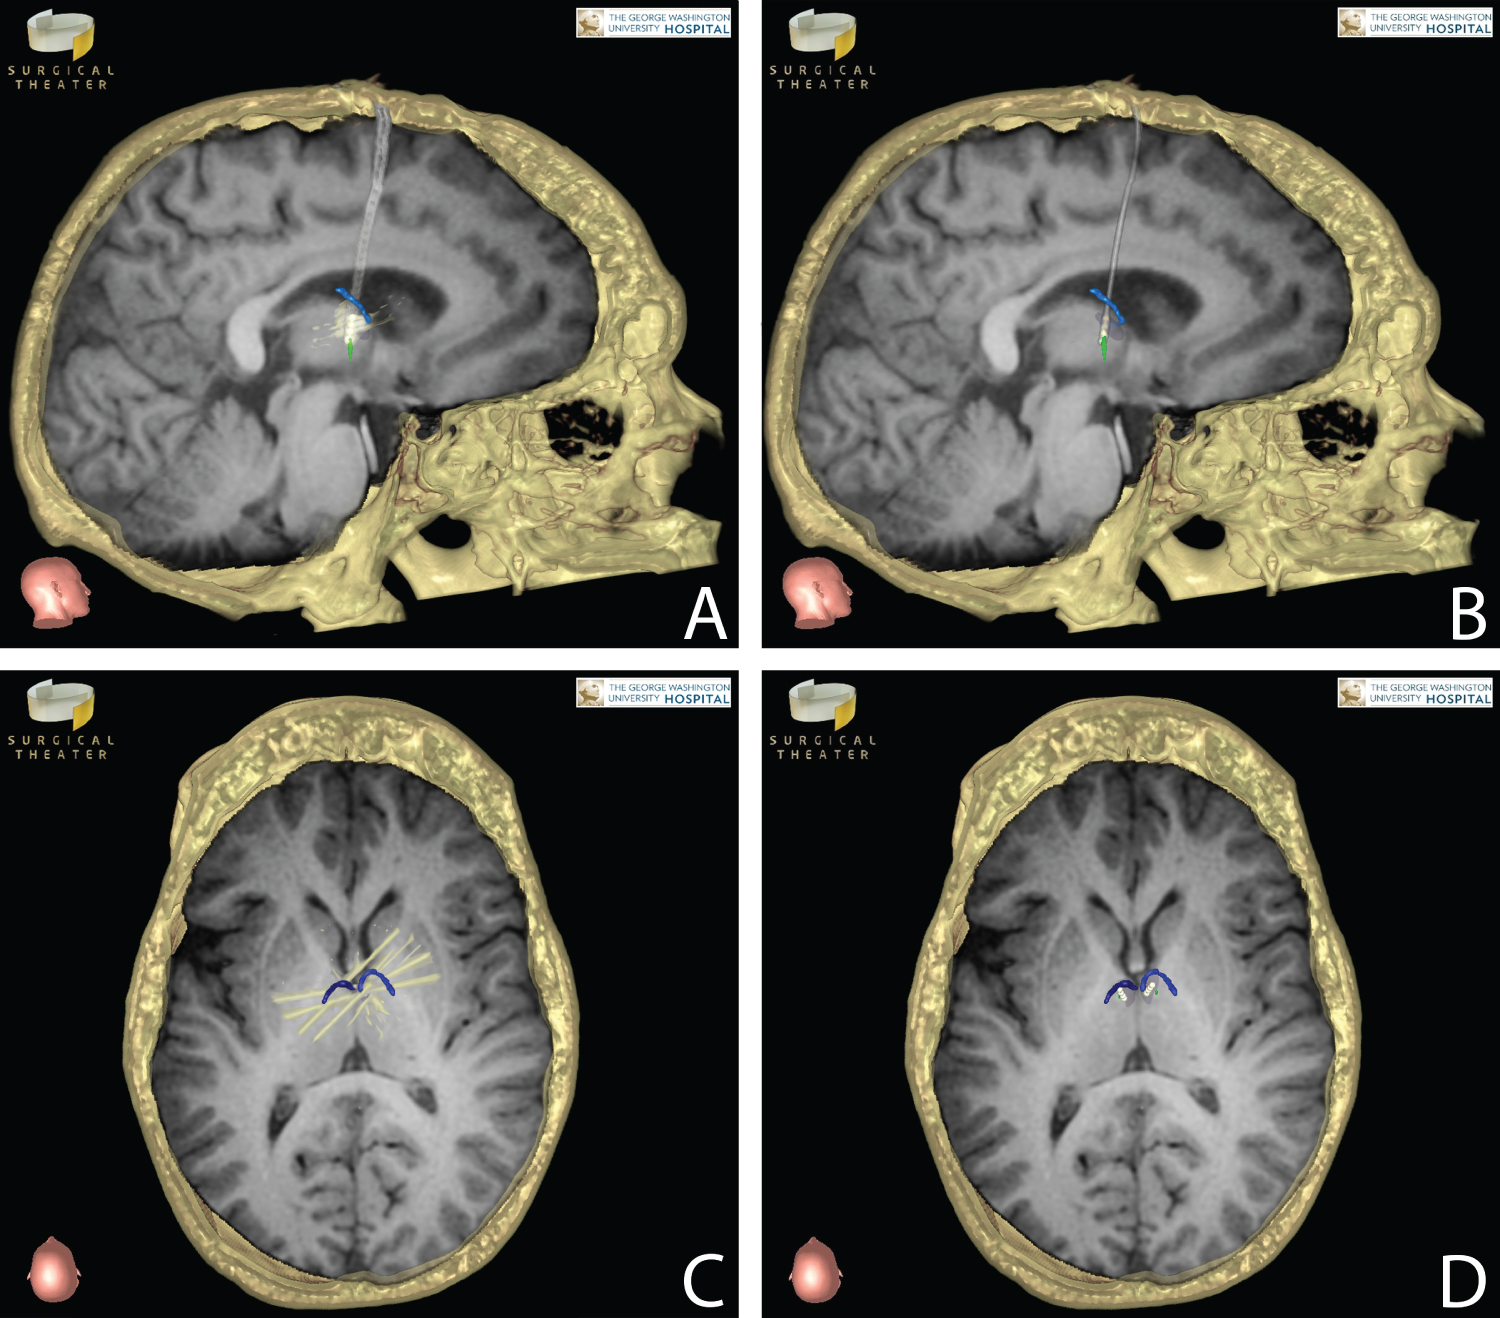

On the morning of surgery, the patient was placed in a Radionics CRW stereotactic frame (Integra Life Sciences Services, Saint Priest, France) and taken for a stereotactic head CT scan with the frame in place. His preoperative MRI was loaded onto the Stealth Station system (Medtronic, Inc., Minneapolis, MN) and merged with the stereotactic CT for surgical planning. Precision VR software (Surgical Theater, Inc., Cleveland, OH) was used to create a 360-degree Virtual Reality (VR) reconstruction of the patient's brain with the anterior thalamic nuclei, mammilothalamic tracts, and major blood vessels identified using the patient's preoperative imaging. This VR model was used in conjunction with the Stealth Neuronavigation software to plan the target and entry points (on the left and right frontal bones) as well as the electrode trajectories. These were designed to avoid the thalamostriate veins along the surface of the thalamus, any large arteries or veins along the electrode path, and the choroid plexus (since a transventricular trajectory was chosen). Entry points were near the coronal suture and approximately 2 cm lateral to the midline on each side. The stereotactic x, y, z, ring, and arc coordinates were then obtained for both approaches from the Stealth Neuronavigation software. After the patient was positioned, prepped, and draped in the standard fashion, the CRW frame was set to the coordinates for the left sided target. A small incision was made after shaving and infiltrating the scalp with local anesthetic. A burr hole was then created with a pneumatic drill assembly, and the dura was opened in a cruciate fashion. The left side was chosen for initial electrode placement since the thalamostriate vein on that side was within 2 mm of the proposed entry point into the thalamus. Pneumocephalus-related brain shift may have placed the vein in the path of the cannula if the right side was entered first. The cannula was passed down to 4 mm above target (just deep to the ventricular surface of the thalamus). Then the cannula stylet was removed and the tip of the 3389 DBS electrode (Medtronic, Inc., Minneapolis, MN) was inserted slightly beyond target - the rostral extent of the left mammilothalamic tract as it abuts the ventral posterior border of the anterior thalamic nucleus. The portion of the 3389 electrode with contacts near the tip is longer than the anterior thalamic nucleus, so only some of the contacts can be used for stimulation of the nucleus. Thus, contacts 0 and 1 were inserted deep to the target, while 2 and 3 were available for stimulation of the anterior thalamic nucleus (Figure 1). The electrode was secured in place at the burr hole site. A lateral skull X-ray was obtained to confirm position. The same procedure was performed on the right side. The neurology team then turned on the stimulation at all 4 contacts bilaterally above 5 volts to confirm the patient did not have any new mood symptoms or neurological changes. The incisions were then closed in a standard fashion. The infraclavicular pulse generator was inserted during a different admission, and a postoperative head CT with stereotactic navigation protocol was obtained to confirm electrode placement. This CT was merged with the preoperative MRI using Precision VR software (Surgical Theater, Inc., Cleveland, OH). CT number 3D grey-level mapping was performed on this software in order to mitigate the typical contact-associated artifact seen on postoperative DBS imaging. Thus, the Neurology team could visually confirm contacts 2 and 3 were appropriate for stimulation.

Figure 1: Each panel represents preoperative stereotactic MRI T1 sequences merged with postoperative CT scans (axial images are not inverted horizontally). Right DBS electrode in sagittal view (A) Prior to 3D grey-level mapping compared with post-mapping image; (B) Mammillothalamic tract (green); (C) Corresponding axial views before and after; (D) Grey-level mapping demonstrate the DBS electrodes in relation to the anterior thalamic nucleus (shaded dark gray). Metallic artifact (white) from the CT scan related to the 4 contacts is shown in panels A and C; this artifact obscures the anterior thalamic nucleus in panel A. The electrode diameter is likewise larger with CT-related distortion in panel A. Portions of the thalamostriate veins (blue) near the electrodes in axial views demonstrate the necessity of slightly more posterior placement of the left electrode, compared to the right, in order to avoid traversing the left thalamostriate vein. View Figure 1